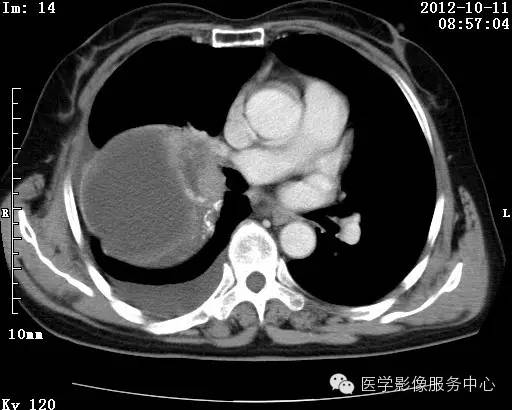

【病例】右肺巨大错构瘤1例CT影像表现

病史:女 65岁咳嗽咳痰 右肺巨大肿块就诊。

理论上肺错构瘤为良性肿瘤,其结节形态、边界、与胸膜关系、与肺门关系、淋巴结肿大及与血管关系均应符合良性肿瘤的特点。

由于不典型错构瘤极易误诊为周围型肺癌和/或结核球,故应与二者鉴别。

结核球患者既往病史中可能有明确的肺结核病史,周围多可见卫 星病灶,增强扫描无强化或仅有包膜强化,此外纵隔 肺门淋巴结多有钙化征象;

周围型肺癌绝大多数边界不光整, 可见短毛刺,钙化不常见,爆米花样钙化更罕见,而 且往往合并有纵隔肺门淋巴结增大增多,患者临床症状较为明显。